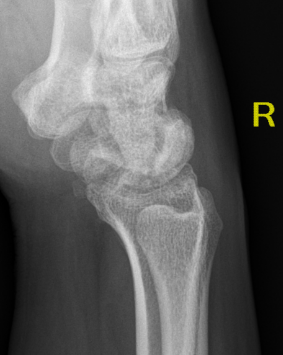

| Stage IIIB | Stage IV |

|---|---|

|

Collapse / fragmentation Scaphoid flexed / Capitate migrates proximally |

Pancarpal osteoarthritis |

![]() |